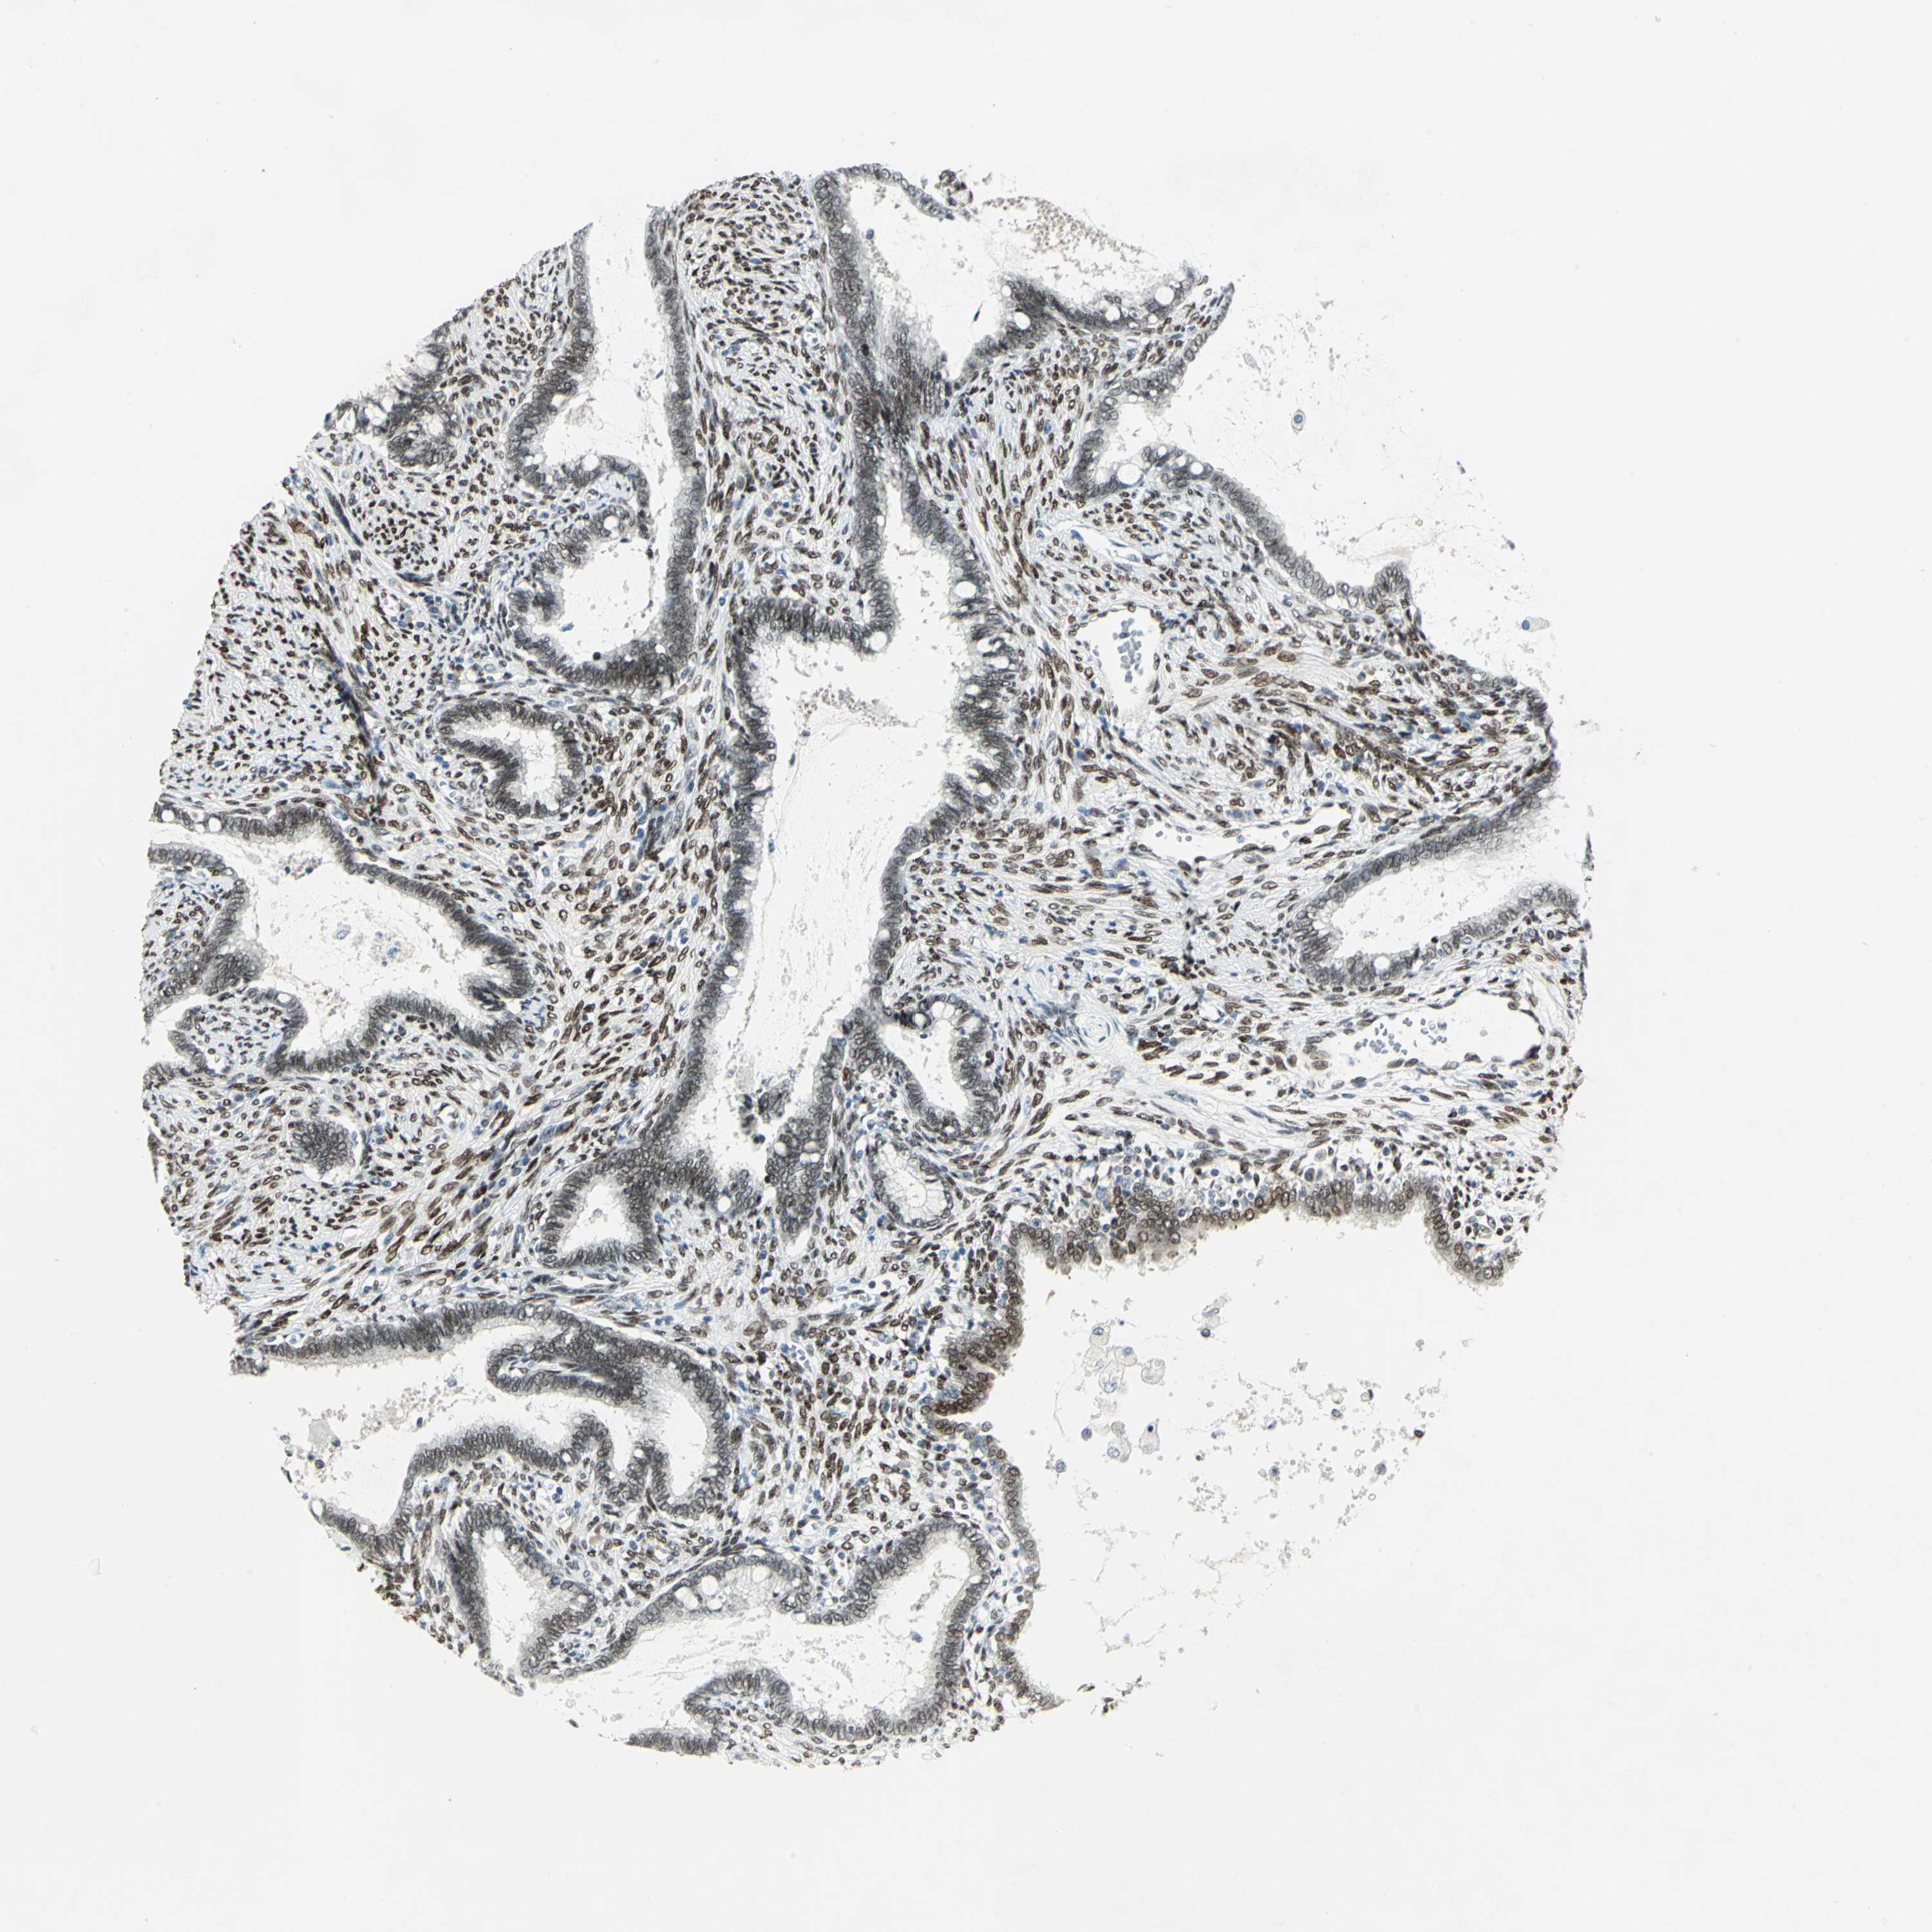

CERVICAL CANCER - Protein expressioni

A mouse-over function shows sample information and annotation data. Click on an image to view it in a full screen mode. Samples can be filtered based on level of antibody staining by selecting one or several of the following categories: high, medium, low and not detected. The assay and annotation is described here.

Note that samples used for immunohistochemistry by the Human Protein Atlas do not correspond to samples in the TCGA dataset.

Antibody stainingi

Antibody staining in the annotated cell types in the current human tissue is reported as not detected, low, medium, or high, based on conventional immunohistochemistry profiling in selected tissues. This score is based on the combination of the staining intensity and fraction of stained cells.

Each image is clickable and will lead to virtual microscopy that enables deeper exploration of all samples and also displays staining intensity scores, fraction scores and subcellular localization as well as patient and tissue information for each sample.

Antibody HPA003256

Antibody CAB004999

Staining

High

Medium

Low

Not detected

Intensity

Strong

Moderate

Weak

Negative

Quantity

>75%

75%-25%

<25%

None

Location

Nuclear

Cytoplasmic/membranous

Cytoplasmic/membranous,nuclear

Squamous cell carcinoma, NOS

Adenocarcinoma, NOS